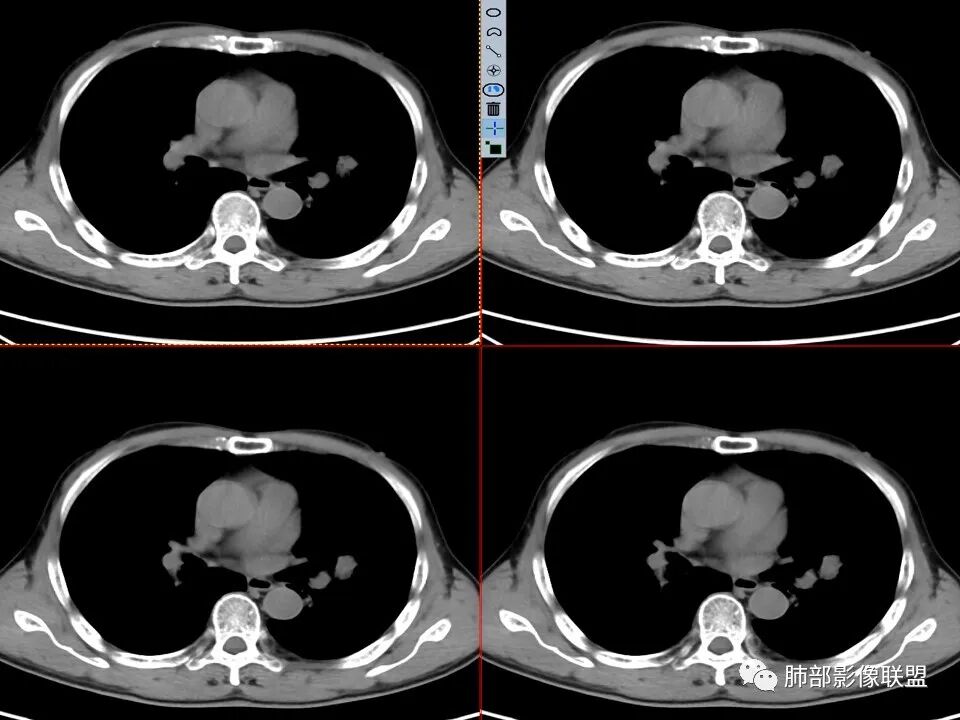

左肺上叶舌段近肺门区不规则结节,密度较均匀,结节边缘平直为主,可见粗短毛刺、毛刺偏软,浅分叶,收缩力不强,膨隆也不明显,周围可见模糊GGO,病灶内部支气管显示不清,病变远端支气管明显扩张,病灶与叶间裂呈宽基底相连,见刀切征,并见叶间裂多发结节影,叶间裂未见明显移位。

患者推测中老年人,无明显临床症状,肺气肿背景不明显,虽然病灶整体炎性征象较多,叶间胸膜多发结节,常规要考虑结核和腺癌,PET-CT肿瘤和炎性病变都可以高摄取,敏感性高,但特异性不高,而且腺癌周围缺乏清晰的磨玻璃及收缩力不强,故暂不考虑;虽然左肺上叶舌段病灶与支气管关系密切,如果周围磨玻璃推测为早期的阻塞性炎症,还有CYFR轻度升高,鳞癌不能除外,但是病灶的整体形态比较符合炎性改变。本病例可惜未行CT增强扫描,无法观察结节的强化特点及病灶内血管走行情况。